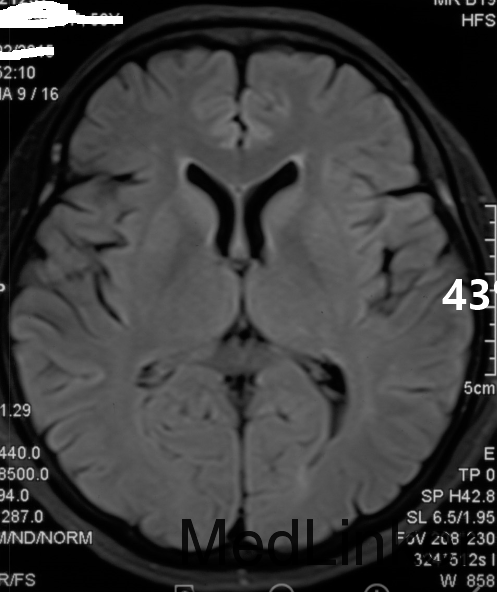

查体:生命体征平稳,神志清楚,反应迟钝,高级意识活动差,检查欠合作,眼球活动可,目光呆滞,有水平向左快向眼震,双侧瞳孔等大等圆,光反射可,双侧鼻唇沟对称,伸舌居中,喜坐位,头颈多偏斜,肩关节旋前,手指呈鸡爪样或屈曲握拳反转,双下肢屈曲,四肢肌力5级,肌张力高,腱反射正常,病理征未引出。共济检查不能配合。 辅助检查:3月25日我院颅脑DWI示双侧豆状核、尾状核稍高信号,双侧颞顶枕叶对称性片状脑回样高信号。3月30日脑电图示:1、重度异常脑电图;2、背景节律无枕区优势,全导为广泛慢波活动,睁眼节律抑制不全;3、发作期间未见明显异常波发放,5月12日脑电图示:1、重度异常脑电图;2、背景节律无枕区优势,全导为周期性双相波或三相波与弥漫性慢波活动交替出现,呈片断性连续发放,后头部为甚;脑脊液常规、生化、培养未见异常,14-3-3蛋白阴性。

诊断:亚急性海绵状脑病(CJD) 治疗并讨论:入院后患者病情进行性加重,精神障碍加重,躁动不安,出现肌阵挛,随后出现无动性缄默,间断全身大发作。予以营养神经(神经节苷脂)、抗癫痫(开蒲兰、地西泮)、抗精神症状(再普乐)等。患者转当地医院治疗。患者早期颅脑MRI未见明显异常,而随病情进一步加重出现特征性影像学及脑电图。